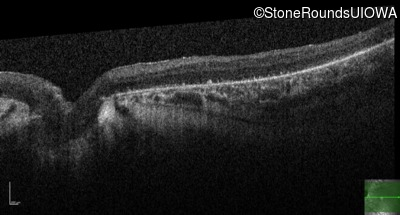

Optical Coherence Tomography - Right - 5/180

Exemplar / OCT Stack